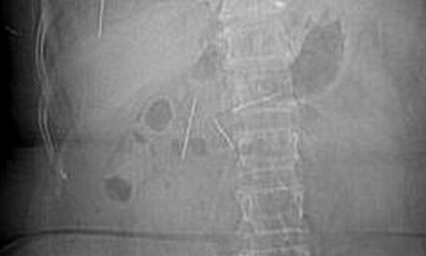

近日,中山大学附属第六医院结直肠肛门外科收到了一位特殊的病人。独居老人听信谣言,以为吞针可以医治腹痛,先后吞下10根针和9块圆形薄片磁铁导致肠穿孔险丧命。